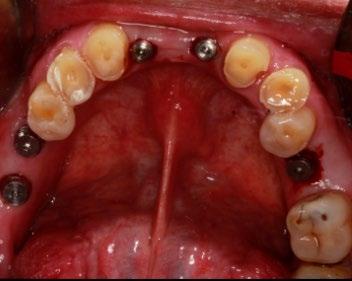

Figura 5. Primera fase quirúrgica de implantes dentales y segunda fase quirúrgica de colocación de tornillos de cicatrización en la zona de los O.D. 16, 15, 24, 26, 36, 32, 42, 46 y 47.

Se montaron los modelos de estudio en un articulador semiajustable Axiomath, aumentando 0.4 mm de DV. Con base en esto, se realizó el encerado diagnóstico (Figura 3). En la fase preventiva, se llevó a cabo una profilaxis con ultrasonido. Posteriormente, se realizaron extracciones de piezas dentarias con mal pronóstico. Se elaboró una guía de silicona basada en el encerado diagnóstico para el mock-up,

En la primera fase quirúrgica se colocaron los implantes dentales en las zonas de las piezas 16, 15, 24, 26, 36, 32, 42, 46 y 47. A los 6 meses se evaluó la osteointegración hueso-implante, y